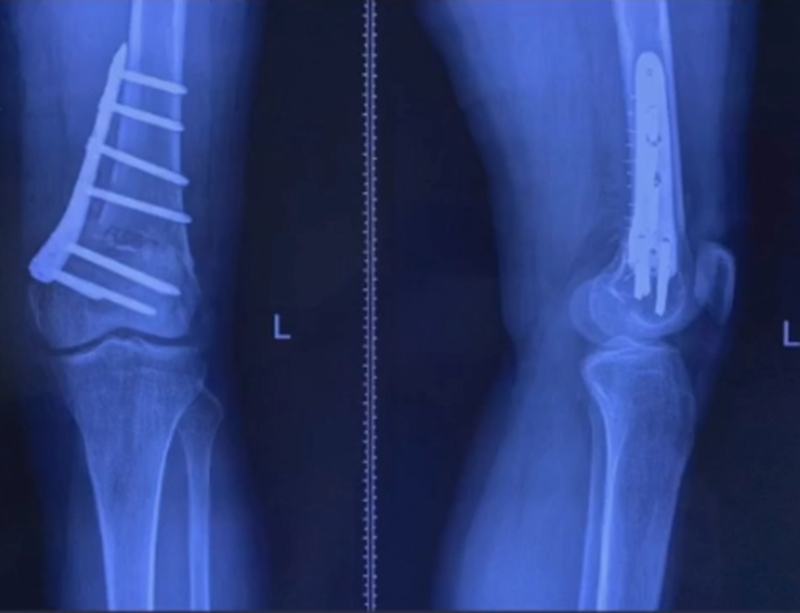

病例,X患者,女,双侧外翻膝,行双侧DFO。

术后6周摔伤,一侧出现膝内翻。

影像学检查显示左侧出现合页断裂。

进行翻修,术前力线显示内翻。

术中发现螺钉松动,截骨端出现坎插迹象。

近端螺钉松开,调整力线,重新固定后,在外侧加小钢板抗旋

术后10周复查,力线较好。